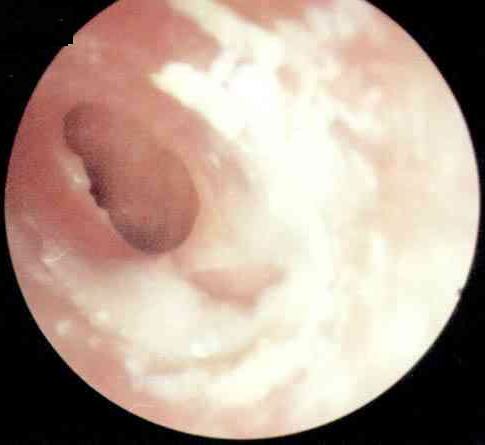

简单地说,胆脂瘤型中耳炎是慢性化脓性中耳炎的一种常见类型。众所周知慢性化脓性中耳炎可分为三种类型:单纯型、骨疡型、胆脂瘤型。其中以胆脂瘤型的后果最为严重。[详细]